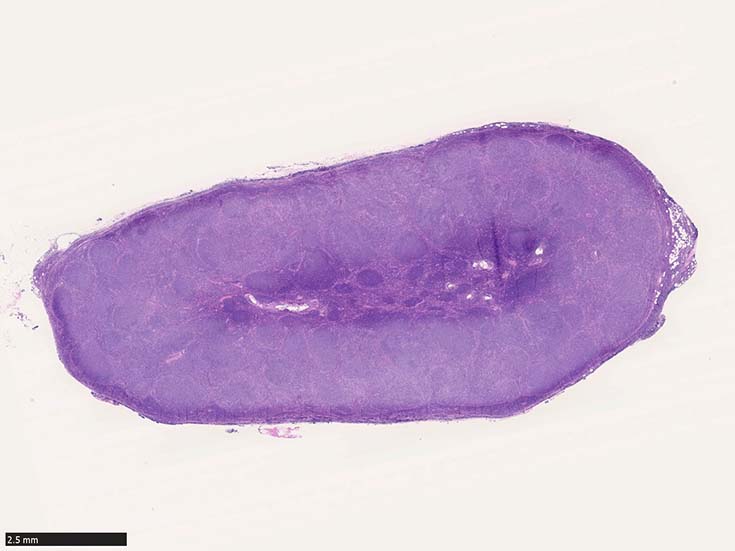

SM02-HEhpf03.jpg

濾胞増殖pattern

低倍率像で濾胞は濾胞間組織にくらべ明るくみえる症例がほとんど。これは小型リンパ球よりやや大型で蒼白な腫瘍細胞が増殖するため。

腫瘍性濾胞は均等にリンパ節全体に分布する。辺縁洞は閉塞され,時に被膜外へ浸潤する。

IWT case 66y.o male

鼠径部リンパ節腫大に気づく. 近医でPETの精査をうけ, 頚部, 縦隔, 腋窩, 鼠径などほぼ全身のリンパ節に腫大が認められた.当院を紹介され受診.鼠径部リンパ節を生検する.

HE所見: サムネイル画像をクリックすると大きな画像がみられます.

左から3つめのFig; x400 HE,増殖細胞はcentrocytes優位